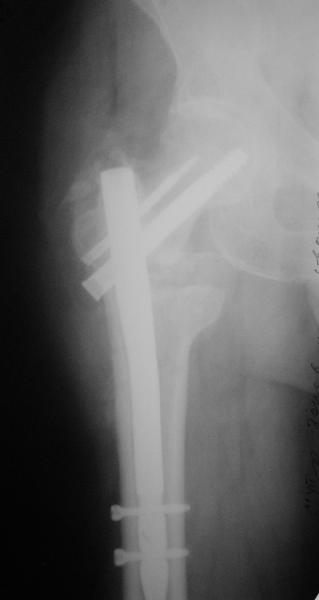

Как предлагали уважаемые коллеги, сегодня наложили спице-стержневой дистрактор таз-бедро, перед этим попробовали закрытую остеоклазию под в/в анестезией, движение в т/б суставе ( или в ложном суставе! ) восстановлен.

Р-снимки сразу п/о, следующий после дистракции, аксиальная - прощу извинения за плохое качество снимков.

Мне кажется надо еще продолжать постепенную дистракцию. И еще которая наверху шейки по моему это осколок от шейки, и она фиксирована оссификатом надвертлужной обл. Поэтому при повторной операции видимо придется открыто мобилизовать т/б сустав.